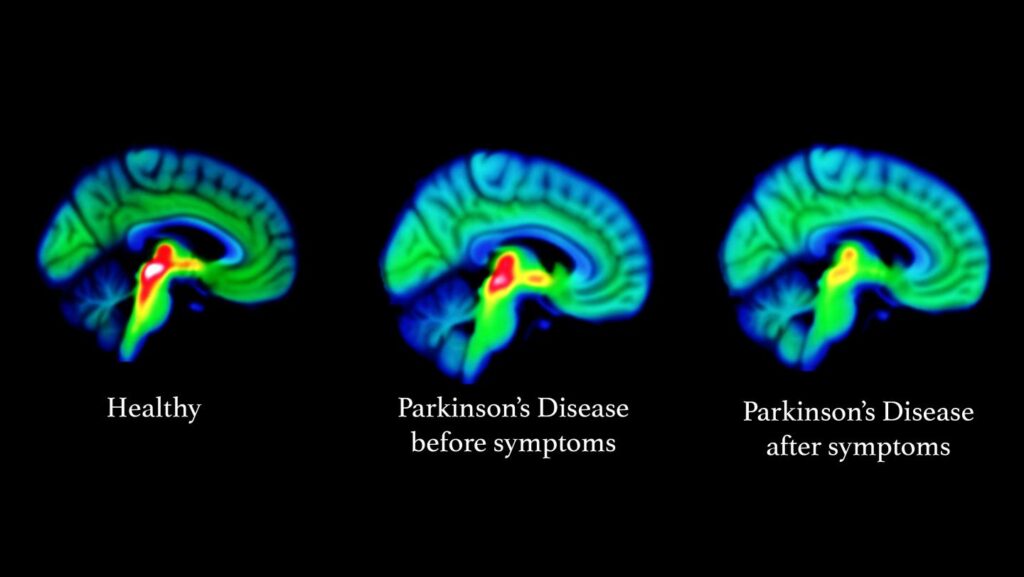

Το Πάρκινσον είναι μια προοδευτική και εξουθενωτική ασθένεια του εγκεφάλου που τελικά θέτει σε κίνδυνο την ικανότητα των ασθενών να περπατούν και ακόμη και να μιλάνε. Η διάγνωσή της είναι πολύπλοκη και στα αρχικά στάδια — αδύνατη. Η συνήθης μέθοδος οπτικοποίησης της δομής του εγκεφάλου χρησιμοποιεί μια τεχνική που ονομάζεται μαγνητική τομογραφία. Ωστόσο, δεν είναι αρκετά ευαίσθητη για να αποκαλύψει τις βιολογικές αλλαγές που λαμβάνουν χώρα στον εγκέφαλο ασθενών με Πάρκινσον και προς το παρόν χρησιμοποιείται, κυρίως, μόνο για τον αποκλεισμό άλλων πιθανών διαγνώσεων.

Οι ερευνητές του Εβραϊκού Πανεπιστημίου της Ιερουσαλήμ (HU), με επικεφαλής τον καθηγητή Aviv Mezer, συνειδητοποίησαν ότι οι κυτταρικές αλλαγές στη νόσο του Πάρκινσον θα μπορούσαν ενδεχομένως να αποκαλυφθούν με την προσαρμογή μιας σχετικής τεχνικής, γνωστής ως ποσοτικής MRI (qMRI). Η μέθοδός τους τους επέτρεψε να εξετάσουν τις μικροδομές μέσα στο τμήμα του βαθέως εγκεφάλου που είναι γνωστό ως ραβδωτό σώμα – ένα όργανο που φθείρεται κατά την εξέλιξη της νόσου του Πάρκινσον. Χρησιμοποιώντας μια νέα μέθοδο ανάλυσης, που αναπτύχθηκε από τον διδακτορικό φοιτητή του Mezer, Elior Drori, αποκαλύφθηκαν καθαρά βιολογικές αλλαγές στον κυτταρικό ιστό του ραβδωτού σώματος. Επιπλέον, μπόρεσαν να αποδείξουν ότι αυτές οι αλλαγές σχετίζονταν με τα πρώιμα στάδια της νόσου του Πάρκινσον και την κινητική δυσλειτουργία των ασθενών. Τα ευρήματά τους δημοσιεύτηκαν σήμερα (15/7) στο περιοδικό Science Advances.

Η qMRI επιτυγχάνει την ευαισθησία της λαμβάνοντας πολλές εικόνες μαγνητικής τομογραφίας χρησιμοποιώντας διαφορετικές ενέργειες διέγερσης — κάτι σαν τη λήψη της ίδιας φωτογραφίας σε διαφορετικά χρώματα φωτισμού. Οι ερευνητές του HU μπόρεσαν να χρησιμοποιήσουν την ανάλυση qMRI για να αποκαλύψουν αλλαγές στη δομή του ιστού σε διακριτές περιοχές του ραβδωτού σώματος. Η δομική ευαισθησία των μετρήσεων μπορούσε να επιτευχθεί προηγουμένως μόνο σε εργαστήρια που εξετάζουν τα εγκεφαλικά κύτταρα ασθενών μετά τη θανάτωση.